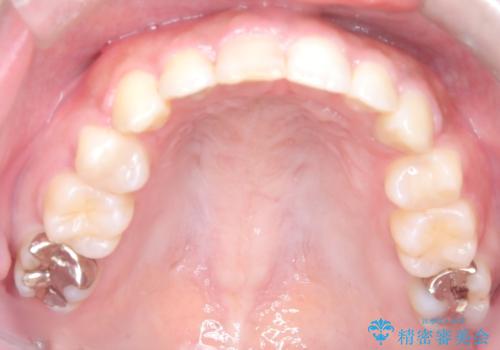

前歯の突出感を改善|上下4本の抜歯と審美ワイヤー矯正でバランスの取れた口元へ

- 患者様は、前歯の突出感を気にされて来院されました。診察の結果、歯列のスペースが不足しており、前歯を後方へ移動させるには抜歯が必要と判断。上下の小臼歯4本を抜歯し、目立ちにくい審美ワイヤー矯正(白いワイヤーと透明ブラケット)を使用して治療を行う計画を立てました。

抜歯によって前歯を下げるためのスペースを確保。その後、審美ワイヤー矯正を用いて、歯列全体のバランスを整えながら前歯を後方へ移動させました。治療後は、横顔のラインが整い、自然な口元になったことで、見た目も噛み合わせも改善しました。患者様からは「口元がすっきりして、自信を持って笑えるようになった」と喜びの声をいただきました。